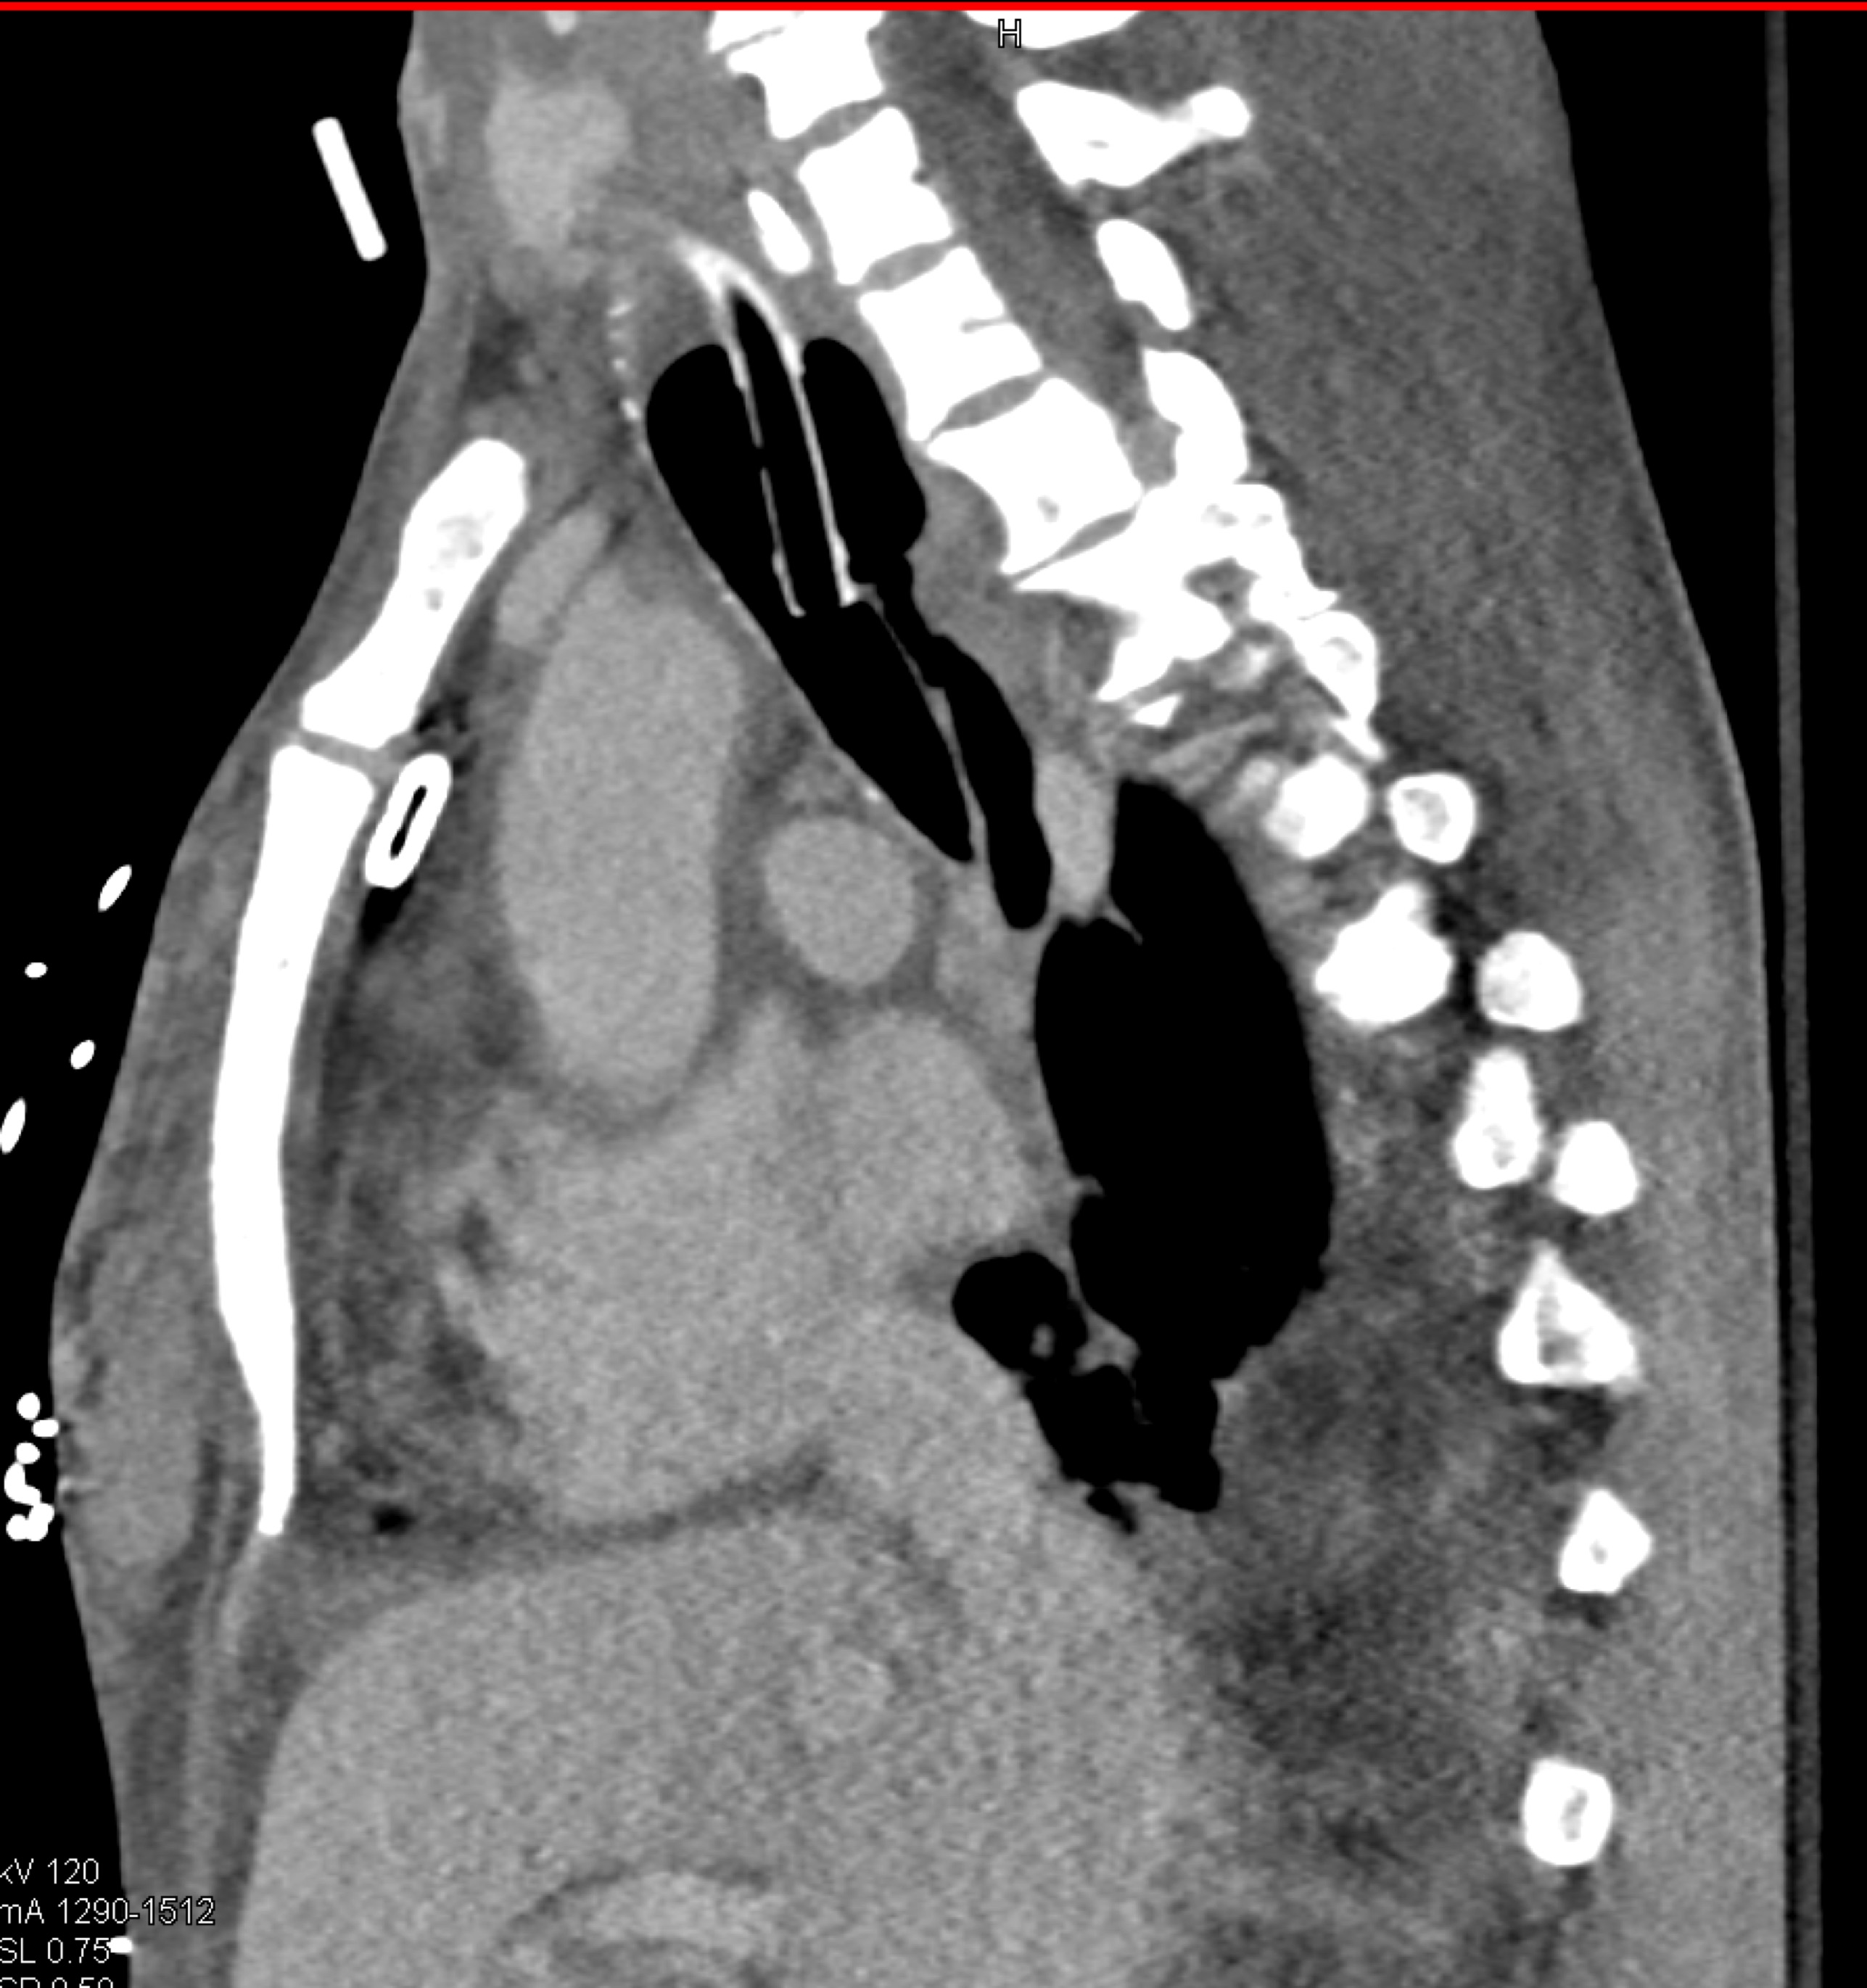

4) The most likely diagnosis in this patient with acute chest pain is?

type A dissection

intramural hematoma

type B dissection

Takayasu’s aortitis